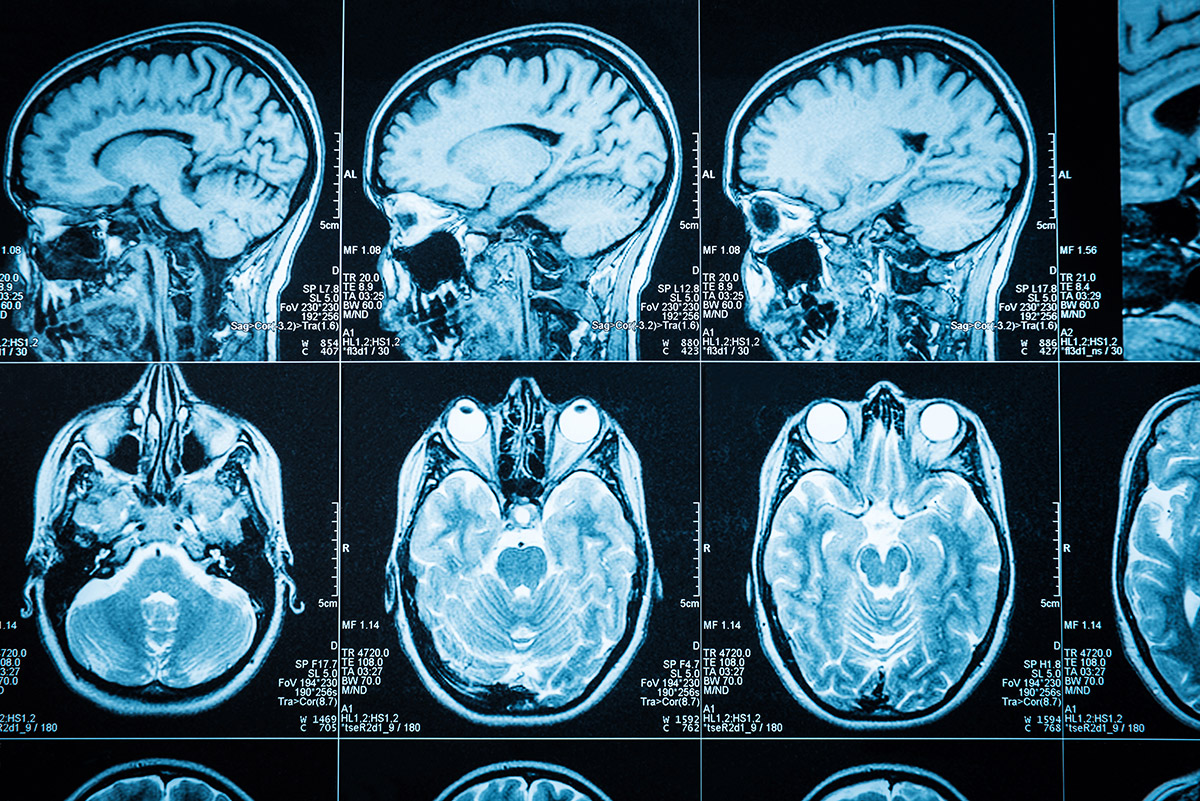

scans mri

brain mri scan coloured sagittal geoff tompkinson se photograph like numbers brains drips vitamin peddling doctors pointless stressed when look

mri brain scan alzheimer using space imaging human software scans wikipedia identifying esa researchers hypothalamus applications pillars medical wiki thalamus

mri brains scan smallest tumor indians hyderabad iit taken cocaine reveals detection brainscan

Mri brain scan alzheimer using space imaging human software scans wikipedia identifying esa researchers hypothalamus applications pillars medical wiki thalamus. Brain scans scan cte concussion athletes football may concussions mainichi nfl players reveal living damage after shows april former boston. Brain mri scan coloured sagittal geoff tompkinson se photograph like numbers brains drips vitamin peddling doctors pointless stressed when look